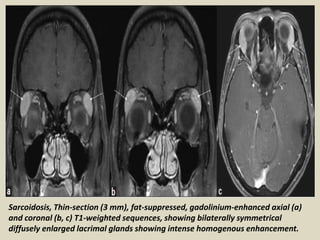

Sarcoidosis, Thin-section (3 mm), fat-suppressed, gadolinium-enhanced axial (a)

and coronal (b, c) T1-weighted sequences, showing bilaterally symmetrical

diffusely enlarged lacrimal glands showing intense homogenous enhancement.